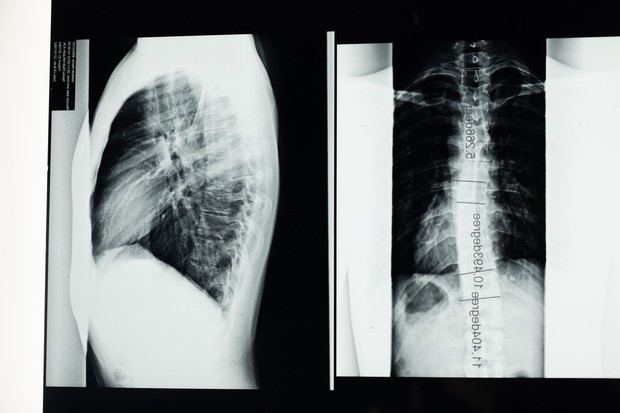

3. Cara mendeketeksi skoliosis

Skoliosis bisa dideteksi saat tulang belakang melengkung. Meski kelihatannya samar, sebaiknya segera waspada dan sembuhkan. Raba dulu bagian fisik tulang belakang. Bila ada budget, segera mintalah CT scan atau rontgen supaya hasilnya valid.